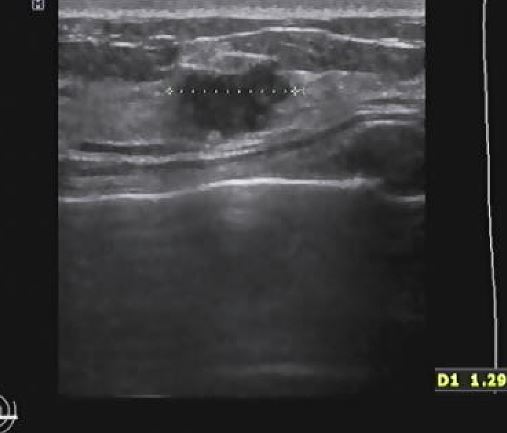

상기환자 외부검사상 이상소견으로 내원하신 40대 여성분으로 조직검사 시행후

유방암으로 진단되었읍니다.